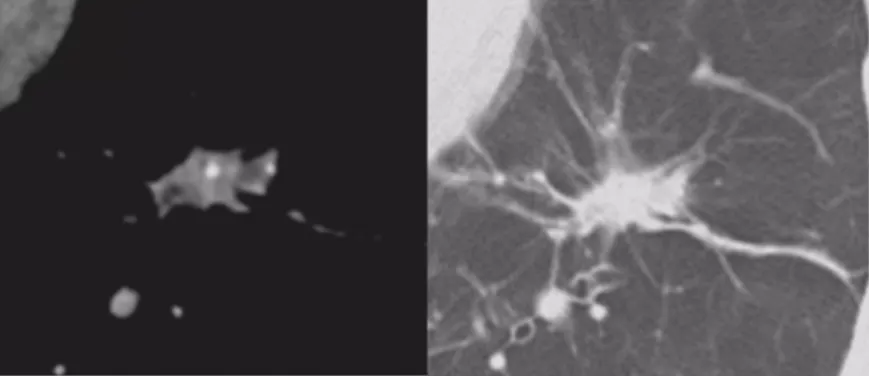

微小结节影像特征

国内、国外都有学者做微小结节相关的研究,以上是张国桢教授的书中所描述的征象。肿瘤的生长需要血管,没有供血的话无法生长。肿瘤的供血很丰富,里面血管很紊乱。这个时候如果我们用现代增强CT扫描,用薄层CT、三维重建,可以看到滋养血管进入肿瘤,我们叫做肿瘤微血管移动征。如果「肿瘤血管」增生形成杂乱新生的毛细血管网,我们叫做联通征。这有助于肺癌的早期诊断。

微小结节的影像特征——周围血管特征

现在有数字肺软件等多种技术,可以对血管进行定量的分析,显示出立体结构,观察结节有多少个血管、进去的角度怎么样、指向如何等等,这些都非常有意义。